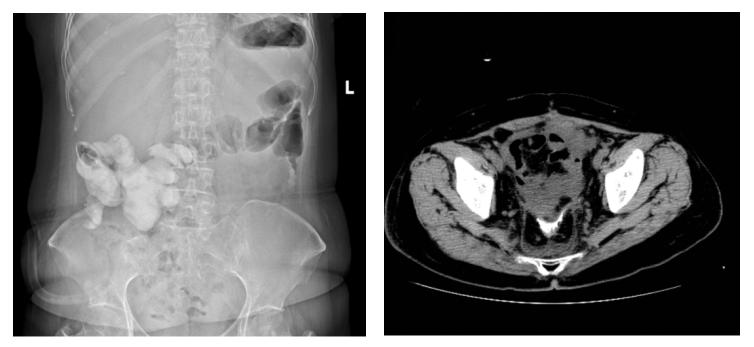

于爱军团队凭借谨慎的术前评估、个体化的手术方案和高超的手术技术,于2025年7月成功为患者邓女士(化名)施行了卵巢癌超根治手术,并应用支架法肠转流术替代了传统造口。术后第二周复查CT及腹部平片可见完整支架影(如图3)。

图3:术后盆腔CT及腹部平片可见完整小肠支架影子(箭头)

(图源:浙江省肿瘤医院)